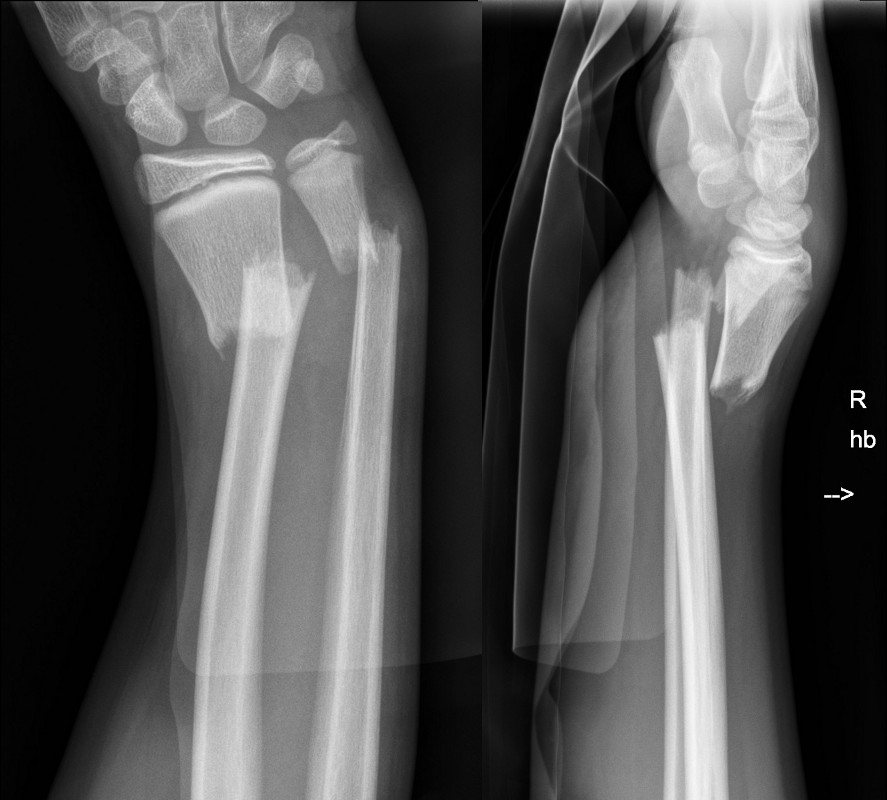

Buckle fractures that should not be managed in a wrist splint

Left image: Buckle fracture with volar angulation (see arrow)

Right image: Disruption of cortex of volar aspect of radius (see arrow)